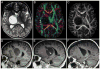

Methods: The authors present a retrospective review of their experience with 10 children presenting between 3 and 15 years of age with a thalamopeduncular syndrome. Formal preoperative MR imaging was obtained in all patients, and diffusion tensor (DT) imaging was performed in 9 patients. Postoperative MR imaging was obtained to evaluate the extent of tumor resection. A prospective analysis of clinical outcomes was then conducted by the senior author.

Results: Pilocytic astrocytoma was the pathological diagnosis in 9 cases, and the other was fibrillary astrocytoma. Seven of 9 pilocytic astrocytomas were completely resected. Radical surgery was avoided in 1 child after DT imaging revealed that the corticospinal tract (CST) coursed through the center of the tumor, consistent with the infiltrative nature of fibrillary astrocytoma as identified by stereotactic biopsy. In 8 patients, tractography served as an important adjunct for designing a surgical approach that spared the CST. In 6 cases the CSTs were pushed anterolaterally, making a transsylvian approach a poor choice, as was evidenced by the first patient in the series, who underwent operation prior to the advent of tractography, and who awoke with a dense contralateral hemiparesis. Thus, subsequent patients with this deviation pattern underwent a transcortical approach via the middle temporal gyrus. One patient exhibited medial deviation of the tracts and another had lateral deviation, facilitating a transtemporal and a transfrontal approach, respectively.